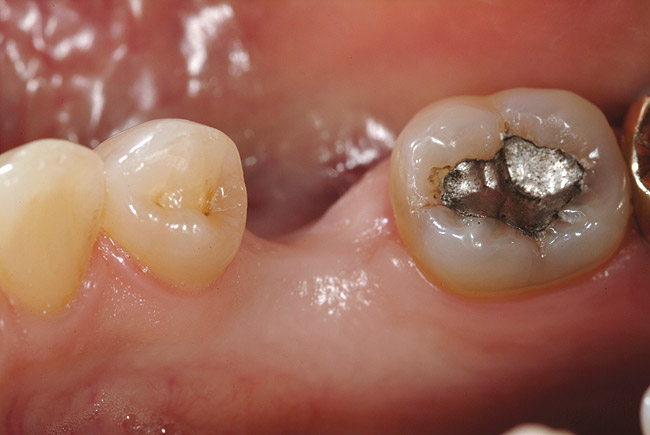

Figure 6a  Missing mandibular premolar; the patient has declined the placement and restoration of missing tooth with an implant. The clinical decision was for a fiber FPD.

Figure 6a